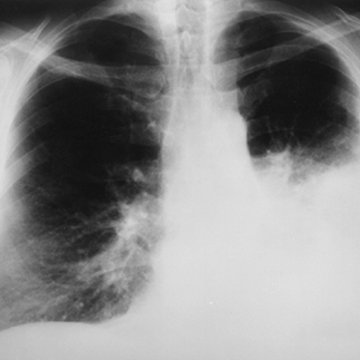

Fighting tooth and nail to see another day…a mother’s struggle with lung lupus

From actively playing volleyball for the country’s national team, being energetic and travelling, Ruusa Kamwi’s world was partially shattered when she was diagnosed with lung lupus, a condition she says became known only after 11 years of ill health.